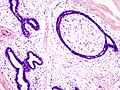

Complex fibroadenoma

- Contain proliferative epithelium which outside and inside a fibroadenoma is associated with an increased risk of malignancy.

Features:[11]

- Apocrine metaplasia.

- Cysts > 3 mm.

- Calcification.

- Sclerosing adenosis.